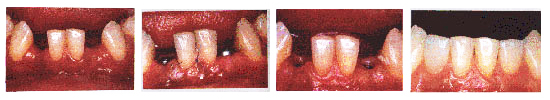

不用磨损健康牙齿,哪儿缺种哪儿。

稳固、咀嚼功能得到最佳的恢复。

感觉舒适,自然美观,形态逼真。

人工种植牙通常可以长久使用。经调查发现人工种植牙的脱落率低于人类自然牙的脱落率。有40年以上还在完好使用的人工种植牙的病例。